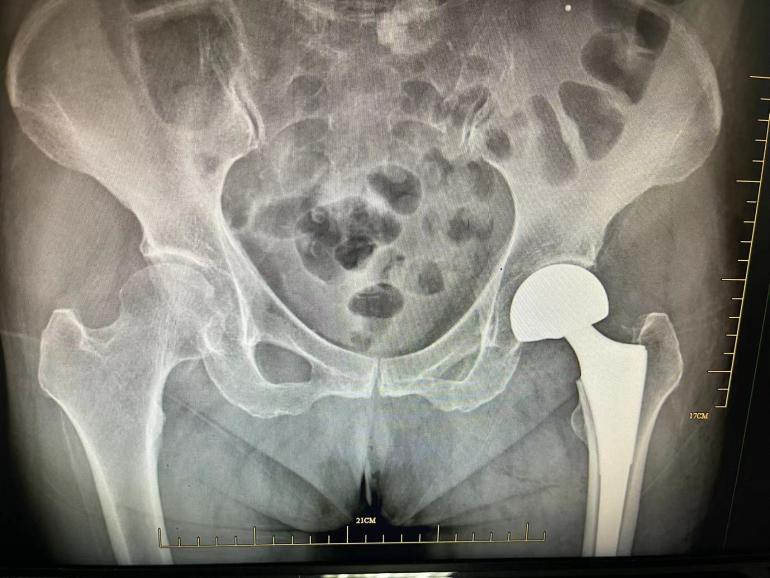

髖部骨折主要是股骨粗隆間骨折和股骨頸骨折,臺(tái)州市中醫(yī)院骨傷科研究室守正創(chuàng)新,針對(duì)老年髖部骨折,采取中西醫(yī)結(jié)合的方法,在中醫(yī)藥補(bǔ)益氣血、活血化瘀等基礎(chǔ)上,可予以閉合復(fù)位內(nèi)固定手術(shù)和人工股骨頭置換手術(shù),取得良好的療效。